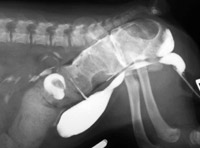

Foto 3: Vaginograma con contraste de un Boston Terrier de 10 semanas de edad ilustra una amplia comunicación entre la pared dorsal del vestíbulo y el recto

Un vaginograma con contraste a menudo es útil en la determinación de la longitud y la anchura de la comunicación en los casos con FRV concurrente (Foto 3). Bajo sedación profunda o anestesia general, se puede insertar una pinza curva en la vulva para ayudar a identificar la comunicación con el recto (Foto 4A).